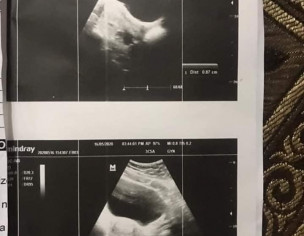

Please post this anonymous,, Mjhy pcos dignose hwa tha,.shadi ko 2 saal hogay hain pehly hmny try ni kia baby k lye,.ab 4 5 mah sy try kar rhy thy lekin ni hwa concieve tou doc ny 22 march ko clomid 50 mg ka cycle dya,.usky bad mai ny due date k bad chek kia tou pregnency ni thi phr 8th april sy mjhy bleeding start hogai kabhi kam kabi zada jo abi tk horai hy,.17 may ko mai ny transamine 500 mg subha sham 5 days khai lekin stop ni hwi bleeding,.ab doc ny kaha hy k Just-n 5mg 21 days khao,,16 may ko may bny scan b karwaya tha usmain sb thek aya hy,.pehly both ovries cystic thi ab koi cyst ni hy,.ab mai kia karo just N start kardo kia?